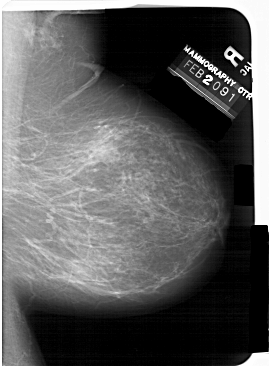

A_1407_1.LEFT_MLO

LEFT_MLO LINES 6121 PIXELS_PER_LINE 4336 BITS_PER_PIXEL 12 RESOLUTION 43.5 OVERLAY